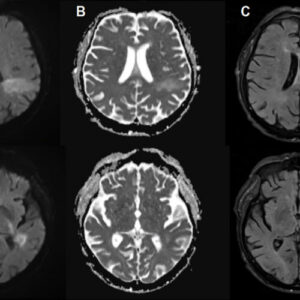

Fatal brain infection was thought to be from profound immune suppression. Not anymore…

You’re likely already infected with a brain-eating virus you’ve never heard of